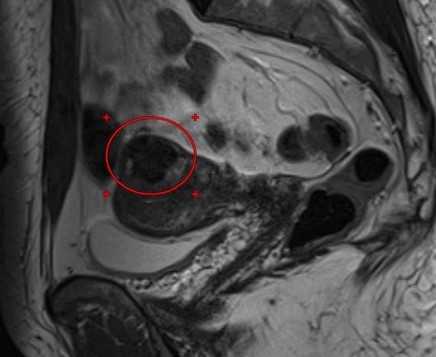

МРТ малого таза в корональной плоскости. В структуре левого яичника отмечаются:

— с толстыми и неровными стенками киста желтого тела (круг),

— функциональная геморрагическая киста (регрессирующее желтое тело).